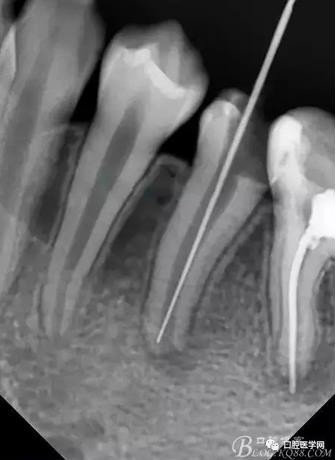

在拔髓的過程中遇到流血,但是不會疼,根管腔超級大,40#根管挫完全不用加壓就直接掉到根尖部,測長直接報警,嚇了一跳,根尖孔這么大,40#根管挫很輕松就超出根尖孔。

擔(dān)心超出根尖孔破壞根尖組織,及時測長再加一張X片,如下圖:

小心翼翼的控制根管長度后進行根管預(yù)備,3%雙氧水與生理鹽水交替沖洗,吸潮紙尖吸干,行氫氧化鈣根管充填,氧化鋅丁香油暫封,醫(yī)囑2周復(fù)診。